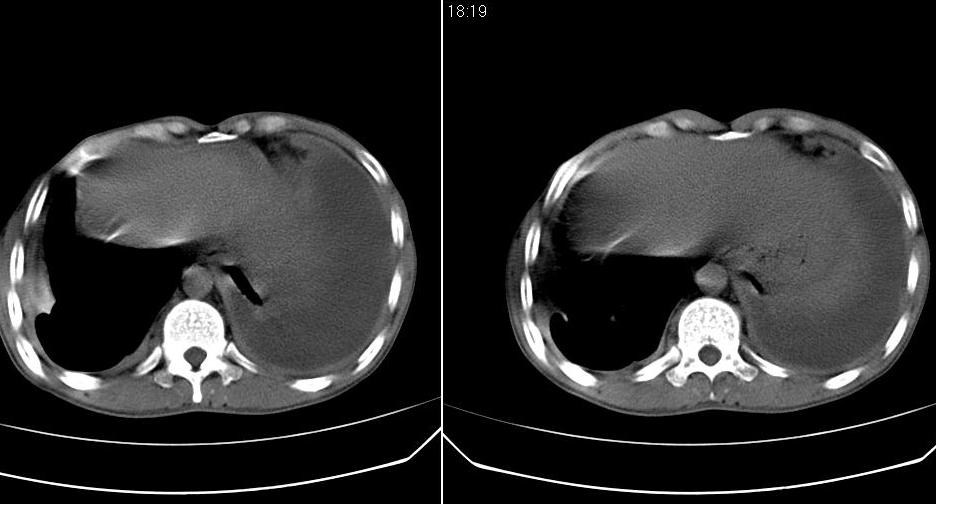

以下是引用苯小孩在2007-6-27 15:09:00的发言:[br]考虑:1、右肺继发性肺结核.2、双侧包裹性积液<胸腔及叶间>3、双侧局部胸膜增厚.[br]建议胸水化验检查.

以下是引用yanghaochen88在2007-6-27 15:08:00的发言:[br]双肺上野散在粟粒状影、包裹性积液、胸膜增厚粘连、叶间积液---tb,至于分型还得结合病史体征细究妥当些。

以下是引用zjzjr在2007-6-27 16:49:00的发言:[br]肺结核、结核性胸膜炎。